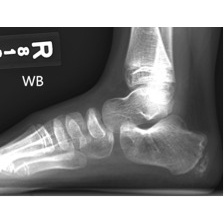

The x-ray of the foot was unremarkable and did not show any soft tissue swelling Case Photo #7